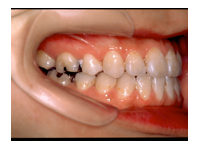

1) 主訴 下あごが出ている、前歯で咬むことができない、しゃべりにくい

2) 診断名 顎変形症(下顎近心変位)

3) 初診時年齢 22歳

5) 抜歯 新規抜歯はなし(ただし上顎左右の第一小臼歯は初診時には既に抜歯されていた)

6) 治療期間 開始時から装置装着まで3か月、術前矯正期間5か月、術前矯正期間3か月、保定期間3年

合計3年11か月